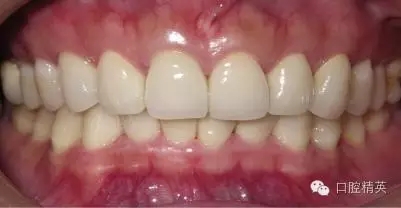

粘固后,對咬合關(guān)系進行初步調(diào)整。三天后,復(fù)查,進一步確認咬合關(guān)系,必要時進行調(diào)整(見圖12)。

LAVA 全瓷冠強度高,顏色自然,邊緣高度密合,切端可見半透明感,整體效果理想,與修復(fù)前(見圖1)相比取得了醫(yī)患均滿意的效果。